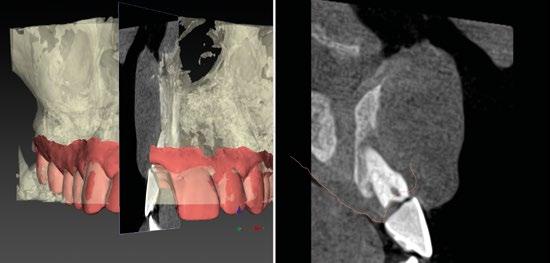

Con todos estos datos fusionados en el DTX StudioTM Implant, lo que vamos a hacer es utilizar la función SMARTSETUP para tener un encerado Virtual que nos permita determinar la posición de la futura restauración del paciente, en función de la cual colocaremos nuestro implante y el aditamento más adecuado. (Figura 8)

En este caso, podemos ver que tenemos un defecto óseo vestibular, se trata de un defecto de una sola pared de la zona a implantar.

Intentamos planificar un implante inmediato y observamos la posibilidad de tener un buen anclaje apical por lo tanto nuestra primera opción va a ser la realización de un implante post extracción con regeneración de la pared vestibular mediate xenoinjerto óseo e injerto de tejido conectivo para mejorar el biotipo. (Figura 9)